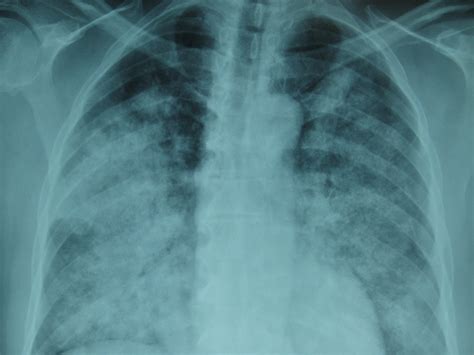

• Imaging Tests: Chest X-rays and CT scans can help visualize the lungs and identify areas of bleeding.

• Bronchoscopy: This procedure involves inserting a thin tube with a camera into the lungs to directly visualize the bleeding.

• diffuse alveolar hemorrhage radiology

• diffuse alveolar hemorrhage cxr